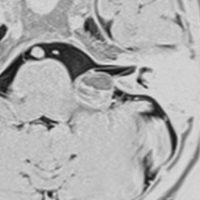

左聴力低下で発症した小脳の海綿状血管腫で,小脳橋角槽に突出するように増大しています。

左上が発症時,次が1ヶ月後,3ヶ月後,4ヶ月後と急速に大きくなったので摘出しました。

静脈奇形を伴っていませんでした。